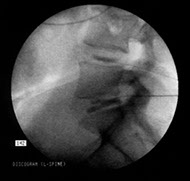

Discography (see image below)

Discography is rarely necessary in the evaluation of acute LBP, and it is certainly not recommended within the first 3 months of treatment. Discography studies can be helpful in patients whose condition has not had a satisfactory response to a well-coordinated rehabilitation program or who have normal or equivocal MRI findings. In such cases, discography may have some benefit in localizing a symptomatic disc as the etiology of nonradicular back pain. (See also the Medscape Reference article Discography.)

A positive discogram must include a concordant pain response, which includes reproduction of the patient's symptoms upon injection of a contrast medium into a symptomatic disc, a nonpainful response upon injection of a contrast medium into control discs, and observed annular pathology on a postdiscography CT scan, if used.

Discography is most often used before the contemplation of surgical fusion for unremitting patient pain that is due to a symptomatic internal disc disruption. Some authors have found discography followed by CT scan to be a more precise technique that may delineate discovertebral pathology with sensitivities that are similar to or better than those of MRI and CT scanning/myelography.

Discography must be used with care because a significant percentage of individuals with positive discography findings improve without surgery. In addition, individuals with underlying psychologic issues tend to overreport pain during discographic injection of the contrast medium. Nonetheless, discographic injection still remains the only quasi-objective provocative test for disc-mediated pain. CT discography has also received attention because it may be a good predictor of surgical outcome following lumbar fusion for patients with intractable back pain.